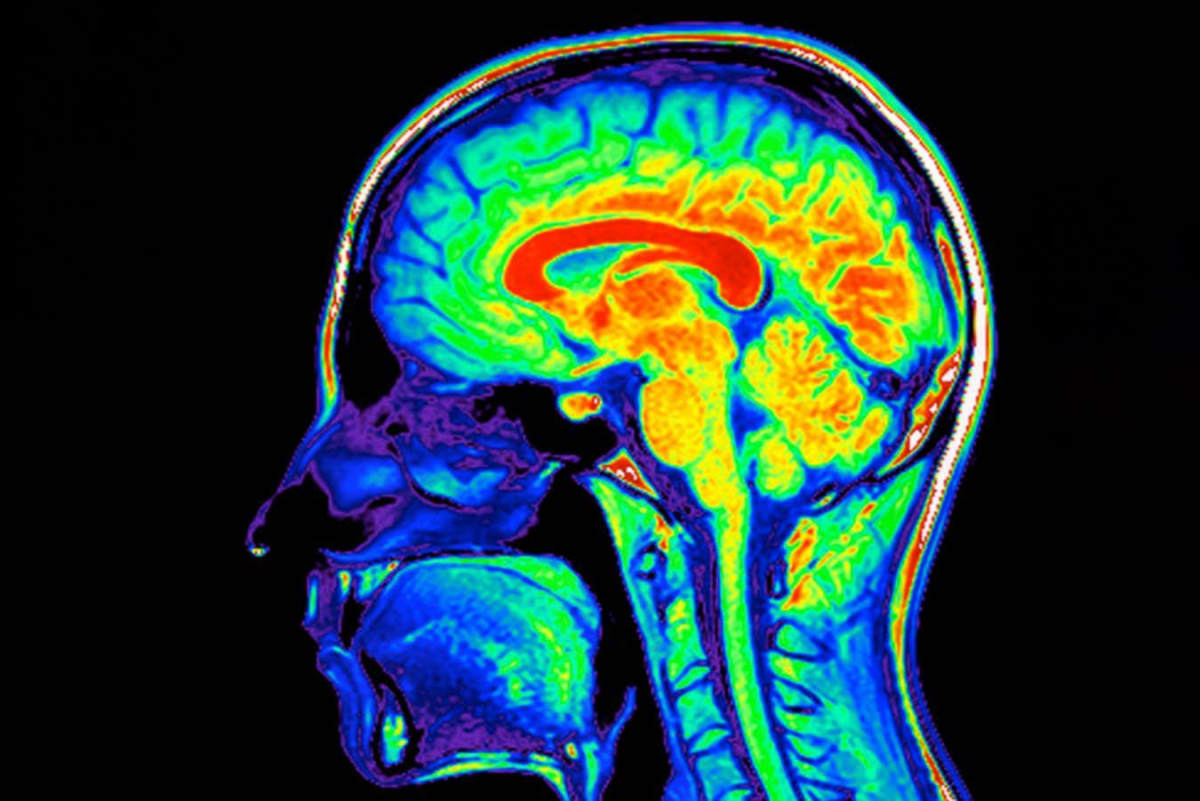

Researchers have discovered the first drug combination that enhances the brain's glymphatic system, a network of channels that naturally clears harmful waste. The treatment pairs a common sedative with blood pressure medication to safely flush out proteins associated with Alzheimer's disease.

The glymphatic system works like a nighttime cleaning crew for your brain, clearing out cellular debris while you sleep. Until now, doctors had no way to boost this natural process. This discovery changes that.